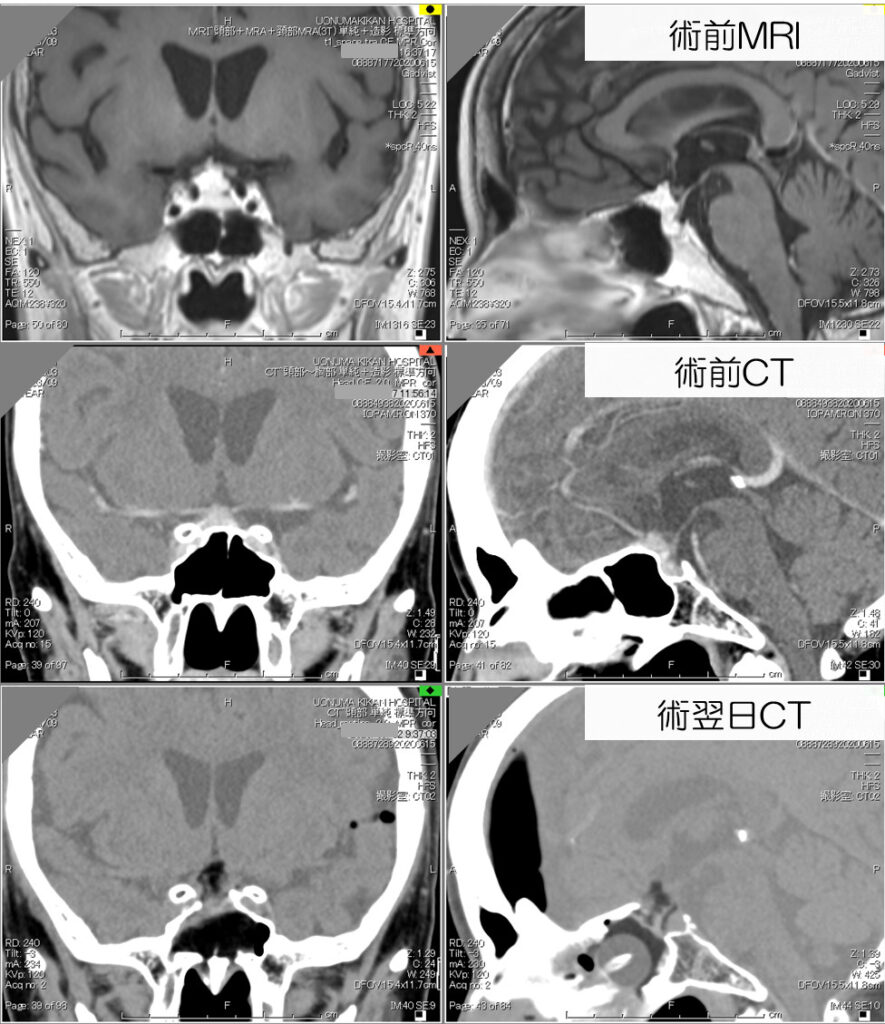

鞍結節部髄膜腫

下垂体腺腫摘出の応用・発展として、鞍結節部髄膜腫を経鼻的に摘出することが出来ます。

従来は開頭手術を要しました。